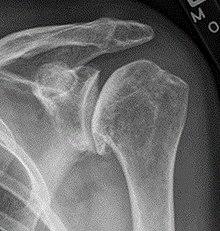

X-ray of shoulder osteoarthritis.

Arthritis of the shoulder causes pain and loss of motion and use of the shoulder.X-rays of the shoulder show loss of the normal space between the ball and socket. X-ray can provide radiographic staging of shoulder osteoarthritis.